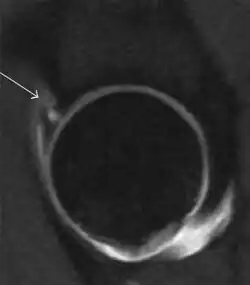

Most of the angles and measurements described in the plain radiograph section can be accurately reproduced on MRI. In addition, the superiority of MRI resolution with intra-articular contrast allows detection of labral and chondral abnormalities that may influence the choice of medical, percutaneous, or surgical management (Figure 9).[1]

Sagittal CT-arthrography showing posteroinferior chondral injury.[1] -

Coronal CT-arthrography (d) showing ligamentum teres tear.[1]